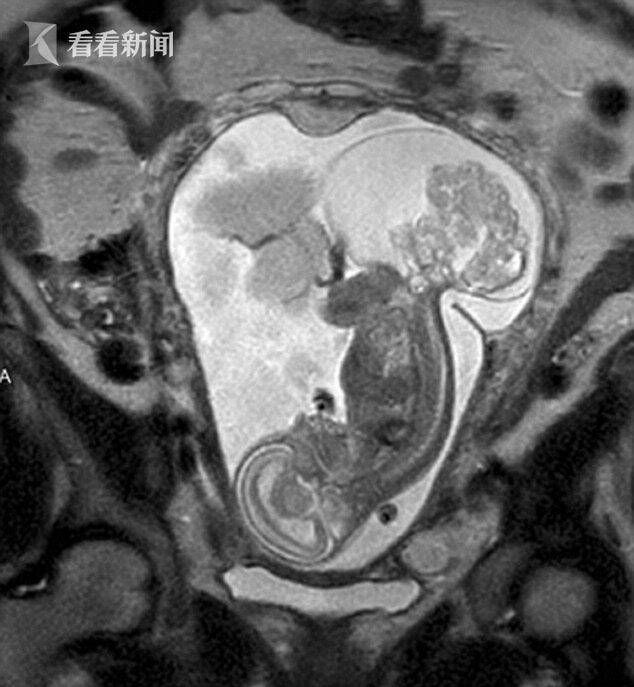

胎儿巨大骶尾部畸胎瘤一例

16.骶尾部畸胎瘤